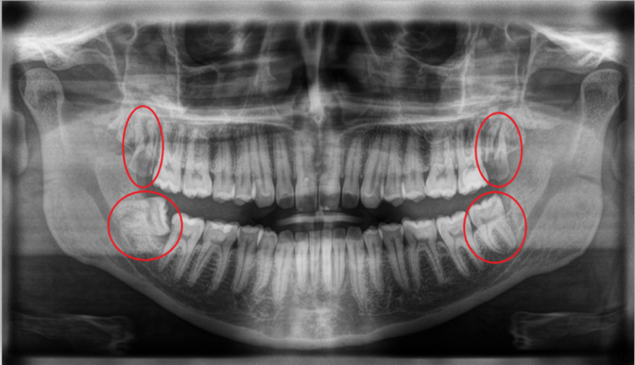

A dental examination and X-ray help determine the position of wisdom teeth and the need for removal.

The first step is a detailed clinical examination and digital X-ray to assess the position of the wisdom tooth and surrounding structures. The second step involves administering local anesthesia to ensure a painless procedure. In some cases, sedation may be recommended. The third step is the surgical removal of the wisdom tooth. If the tooth is impacted, a small incision may be made in the gum and bone to safely extract the tooth. The final step includes cleaning the area and placing sutures if required. Post-operative instructions are provided to support proper healing.